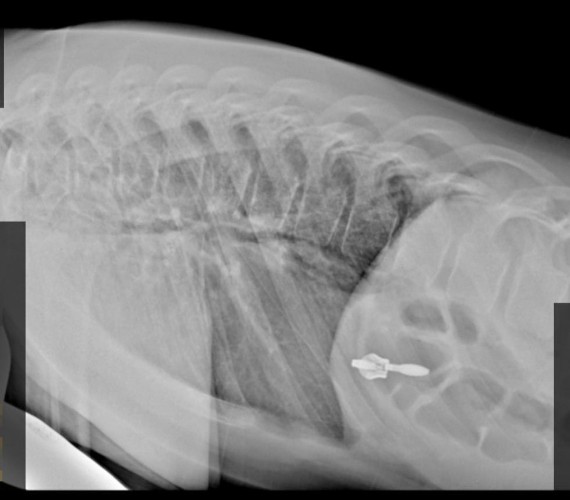

За одни сутки пять детей поступили в травмпункт Ивано-Матрёнинской детской клинической больницы в Иркутске с компрессионными переломами позвоночника. Все пациенты, кроме одного, попали в стационар.